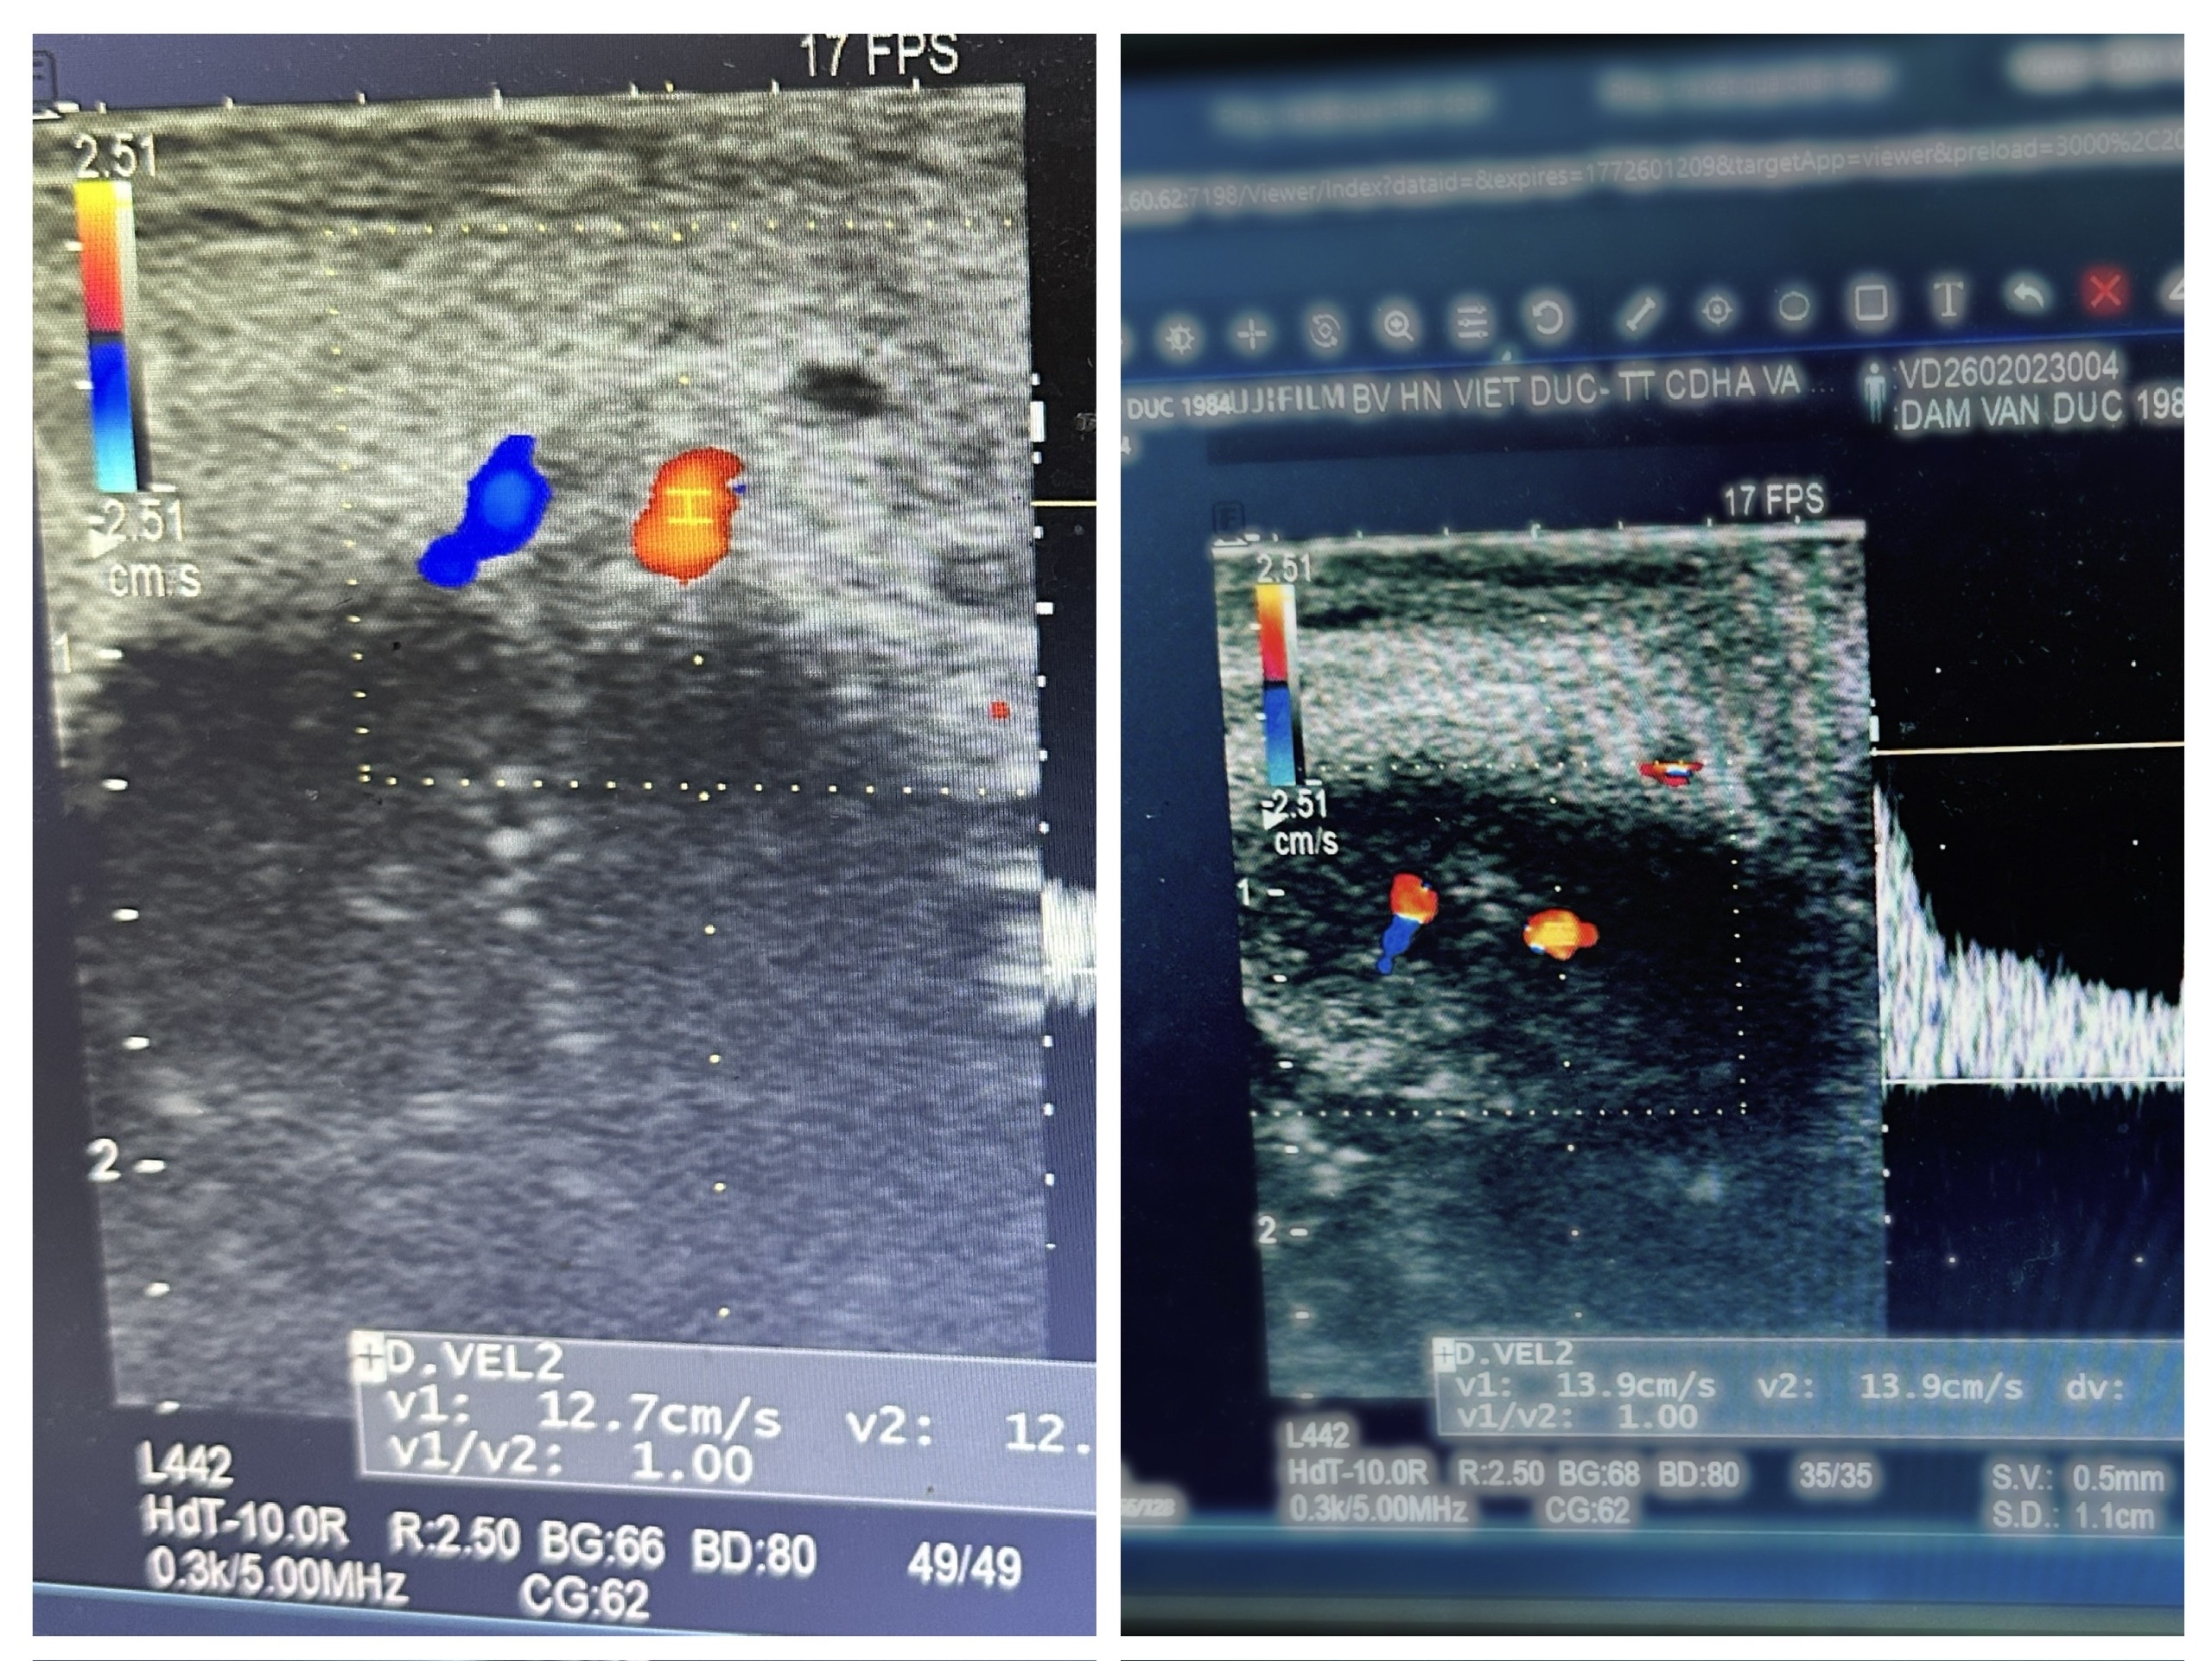

Hình ảnh siêu âm sau phẫu thuật cho thấy máu vào động mạch, tĩnh mạch rất tốt